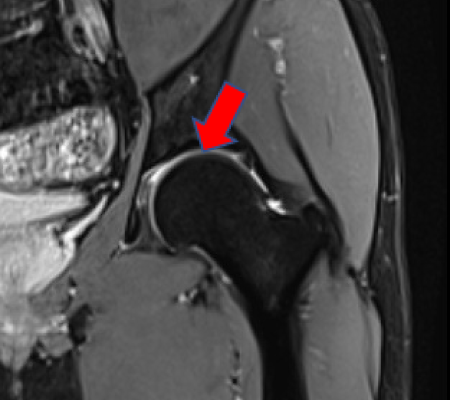

비구순 연골 손상 진단

X-ray, CT, MRI 검사를 통해 고관절에서 충돌이 일어나는 모양인지와 비구순의 파열 정도를 확인합니다.

비구순이 파열된 MRI 영상 (2021.09.07)

ㆍ비구순 연골파열 및 파열된 비구순을 봉합하는고관절 관절내시경 영상 (2021.10.15)

ㆍ환자 동의를 받은 자료이며, 이미지 사진은 실물과 다를 수 있습니다.